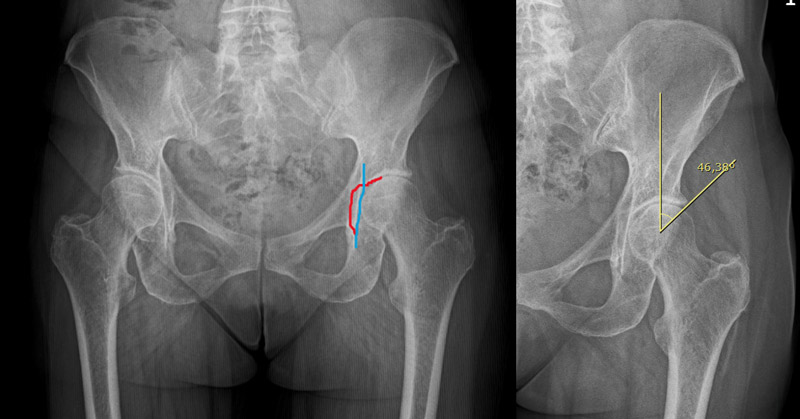

Pre-op X-rays

• Tonnis 1 Hip osteoarthritis ✔️

• Coxa profunda ✔️

• Femoroacetabular impingement Pincer type ✔️

• Anterior hip osteoarthritis ✔️